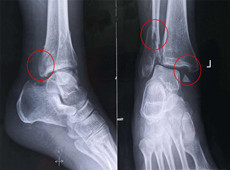

【醫(yī)療科普】踝關(guān)節(jié)骨折的主要類型及其影像學(xué)表現(xiàn)

大家好,我是南京醫(yī)科大學(xué)第二附屬醫(yī)院骨科副主任醫(yī)師王伯堯,從事骨科臨床工作十余年,擁有豐富的骨科臨床經(jīng)驗,主要研究方向為骨科手術(shù)機器人的開發(fā)與臨床應(yīng)用,今天跟大家介紹踝關(guān)節(jié)骨折的幾種常見類型及其在X影像上的表現(xiàn)。接下來跟...